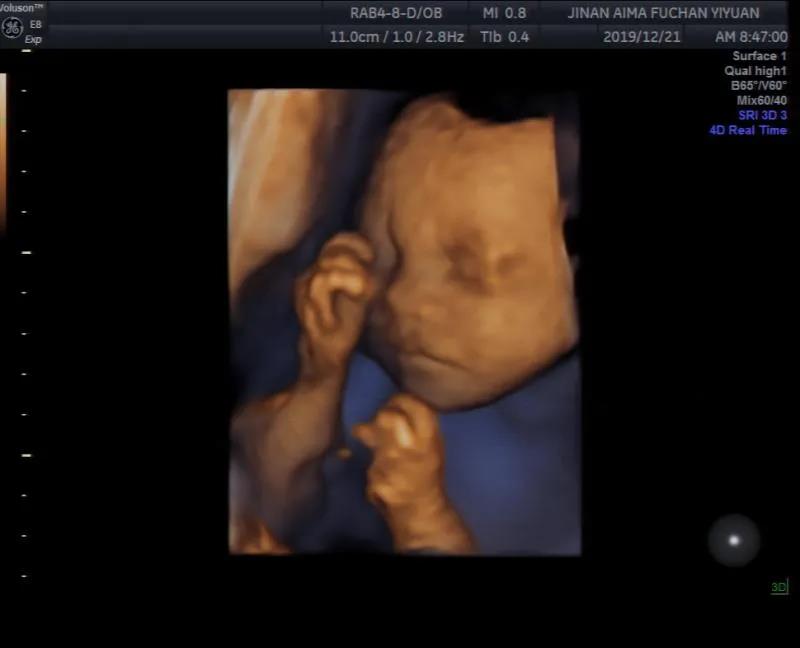

22周-26周—胎儿系统超声检查(四维彩超)

胎儿系统超声检查是发现

胎儿畸形的个重要手段之

胎儿系统超声检查可以检测

胎儿在宫内是否缺氧、肢体运动、

胎儿的吞咽动作等

能够看到胎儿在母体内的活动状况

还可以比较准确地测量羊水量